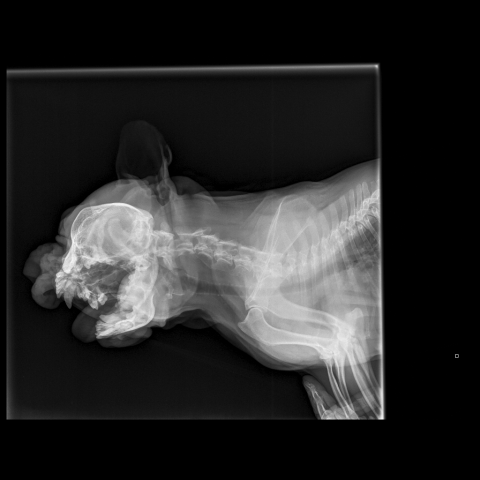

Французский бульдог,6 лет.Стала плохо ходить,что- то с позвоночником.Врачи не могут поставить диагноз.Есть снимки.Помогите!

Снимки хорошие, качественные, но совершенно не информативные. На этих пленках патология не определяется. Но здесь нет снимка, который нужен обязательно - поясничный отдел позвоночника в прямой проекции (такой, как 3-й, но только не шея, а поясница).

Нет,наоборот.Собака сначала стала немного наклонять голову вправо.Когда были на консультации у окулиста,то он обратил внимание на это ,сказал,что есть какие-то изменения в области шеи.Я отсутствовала дома 2 недели.Приехала,собаку вообще не узнала.Крен головы вправо стал еще сильнее,передние ноги как-то ослабли.Она идет,может споткнуться,упасть.Сходили,сделали рентген.снимок.Поставили диагноз:атланто-аксиальная нестабильность шейного отдела,спондилоартроз. Проколола 5 дней:актовегин,папаверин,комбилипн,мидокалм,дексаметазон. Пока делала уколы и еще дней 5 после этого собаке стало легче,а потом опять вернулись к тому, что было.На консультации врач сказал,что дальше просто колоть преднизалон. Я уехала к другому врачу,тот сделал снимки,которые я Вам отослала.Сказал, что диагноз не подтверждает,на пальцах показал, что со спинным мозгом все нормально.С помощью какой-то процедуры (бумаги на работе)обнаружил перфорацию барабанной перепонки.Выписал лечение:цефтриаксон,циклоферон,цебролизин(колола 2 дня,стало хуже),комбилипен.В уши-изотик.Сказал,что может быть у собаки был инсульт.Собаке от лечения хуже.Вот такие дела.